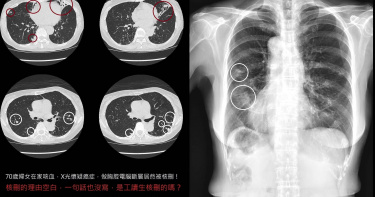

婦咳到吐血「電腦斷層竟被核刪」 醫見理由怒了:出事去告健保署

衛福部4日取消醫療院所掛號費上限,引發相關爭議。胸腔科醫師蘇一峰透露,1名70歲婦人因咳血就醫,X光檢查發現肺部出現好幾塊斑塊,於是安排電腦斷層進一步檢查,結果照出一大堆肺結節,初步判斷為支氣管擴張症,誰知電腦斷層竟被健保核刪,就連理由也沒寫,讓他忍不住痛批「健保就是搞得台灣醫療品質下降的元兇」。蘇一峰今(20日)在臉書粉專發文,「專家都告訴我們,咳血要擔心癌症肺癌!X光有問題一定要小心!安排電腦斷層進一步檢查!」他提到,1名70歲婦人因咳血就醫,照了X光發現肺部出現斑塊,「安排電腦斷層發現一大堆肺結節!!支氣管擴張症!」沒想到,電腦斷層檢查竟被健保核刪。醫師進一步指出,最誇張的是核刪理由竟然空白,上面連1個字也沒寫,甚至還是匿名核刪,讓他傻眼直呼「請問這真的是醫師審核嗎?看起來像工讀生隨便亂審」。蘇一峰直言,健保就是害台灣醫療品質下降的元兇,「今天這樣亂核刪,是不是告訴醫師以後病人咳血有肺結節也不要管他!?乾脆推出AI醫師來按照健保規定看診!民眾出事去告健保署!」貼文曝光後,不少網友留言「朽木為官,禽獸食祿,人民自求多福」、「健保沒錢就亂刪,叫醫生做功德?刪CT!不然博杯來診斷好了」、「現在健保要調整掛號費無上限!如果連電腦斷層檢查的費用都要刪,這是叫台灣人民生活越來越辛苦」、「真的是刪的莫名其妙啊!我們的健保都是繳假的」、「被刪是醫院要吸收成本,但最終收到影響的還是民眾」。